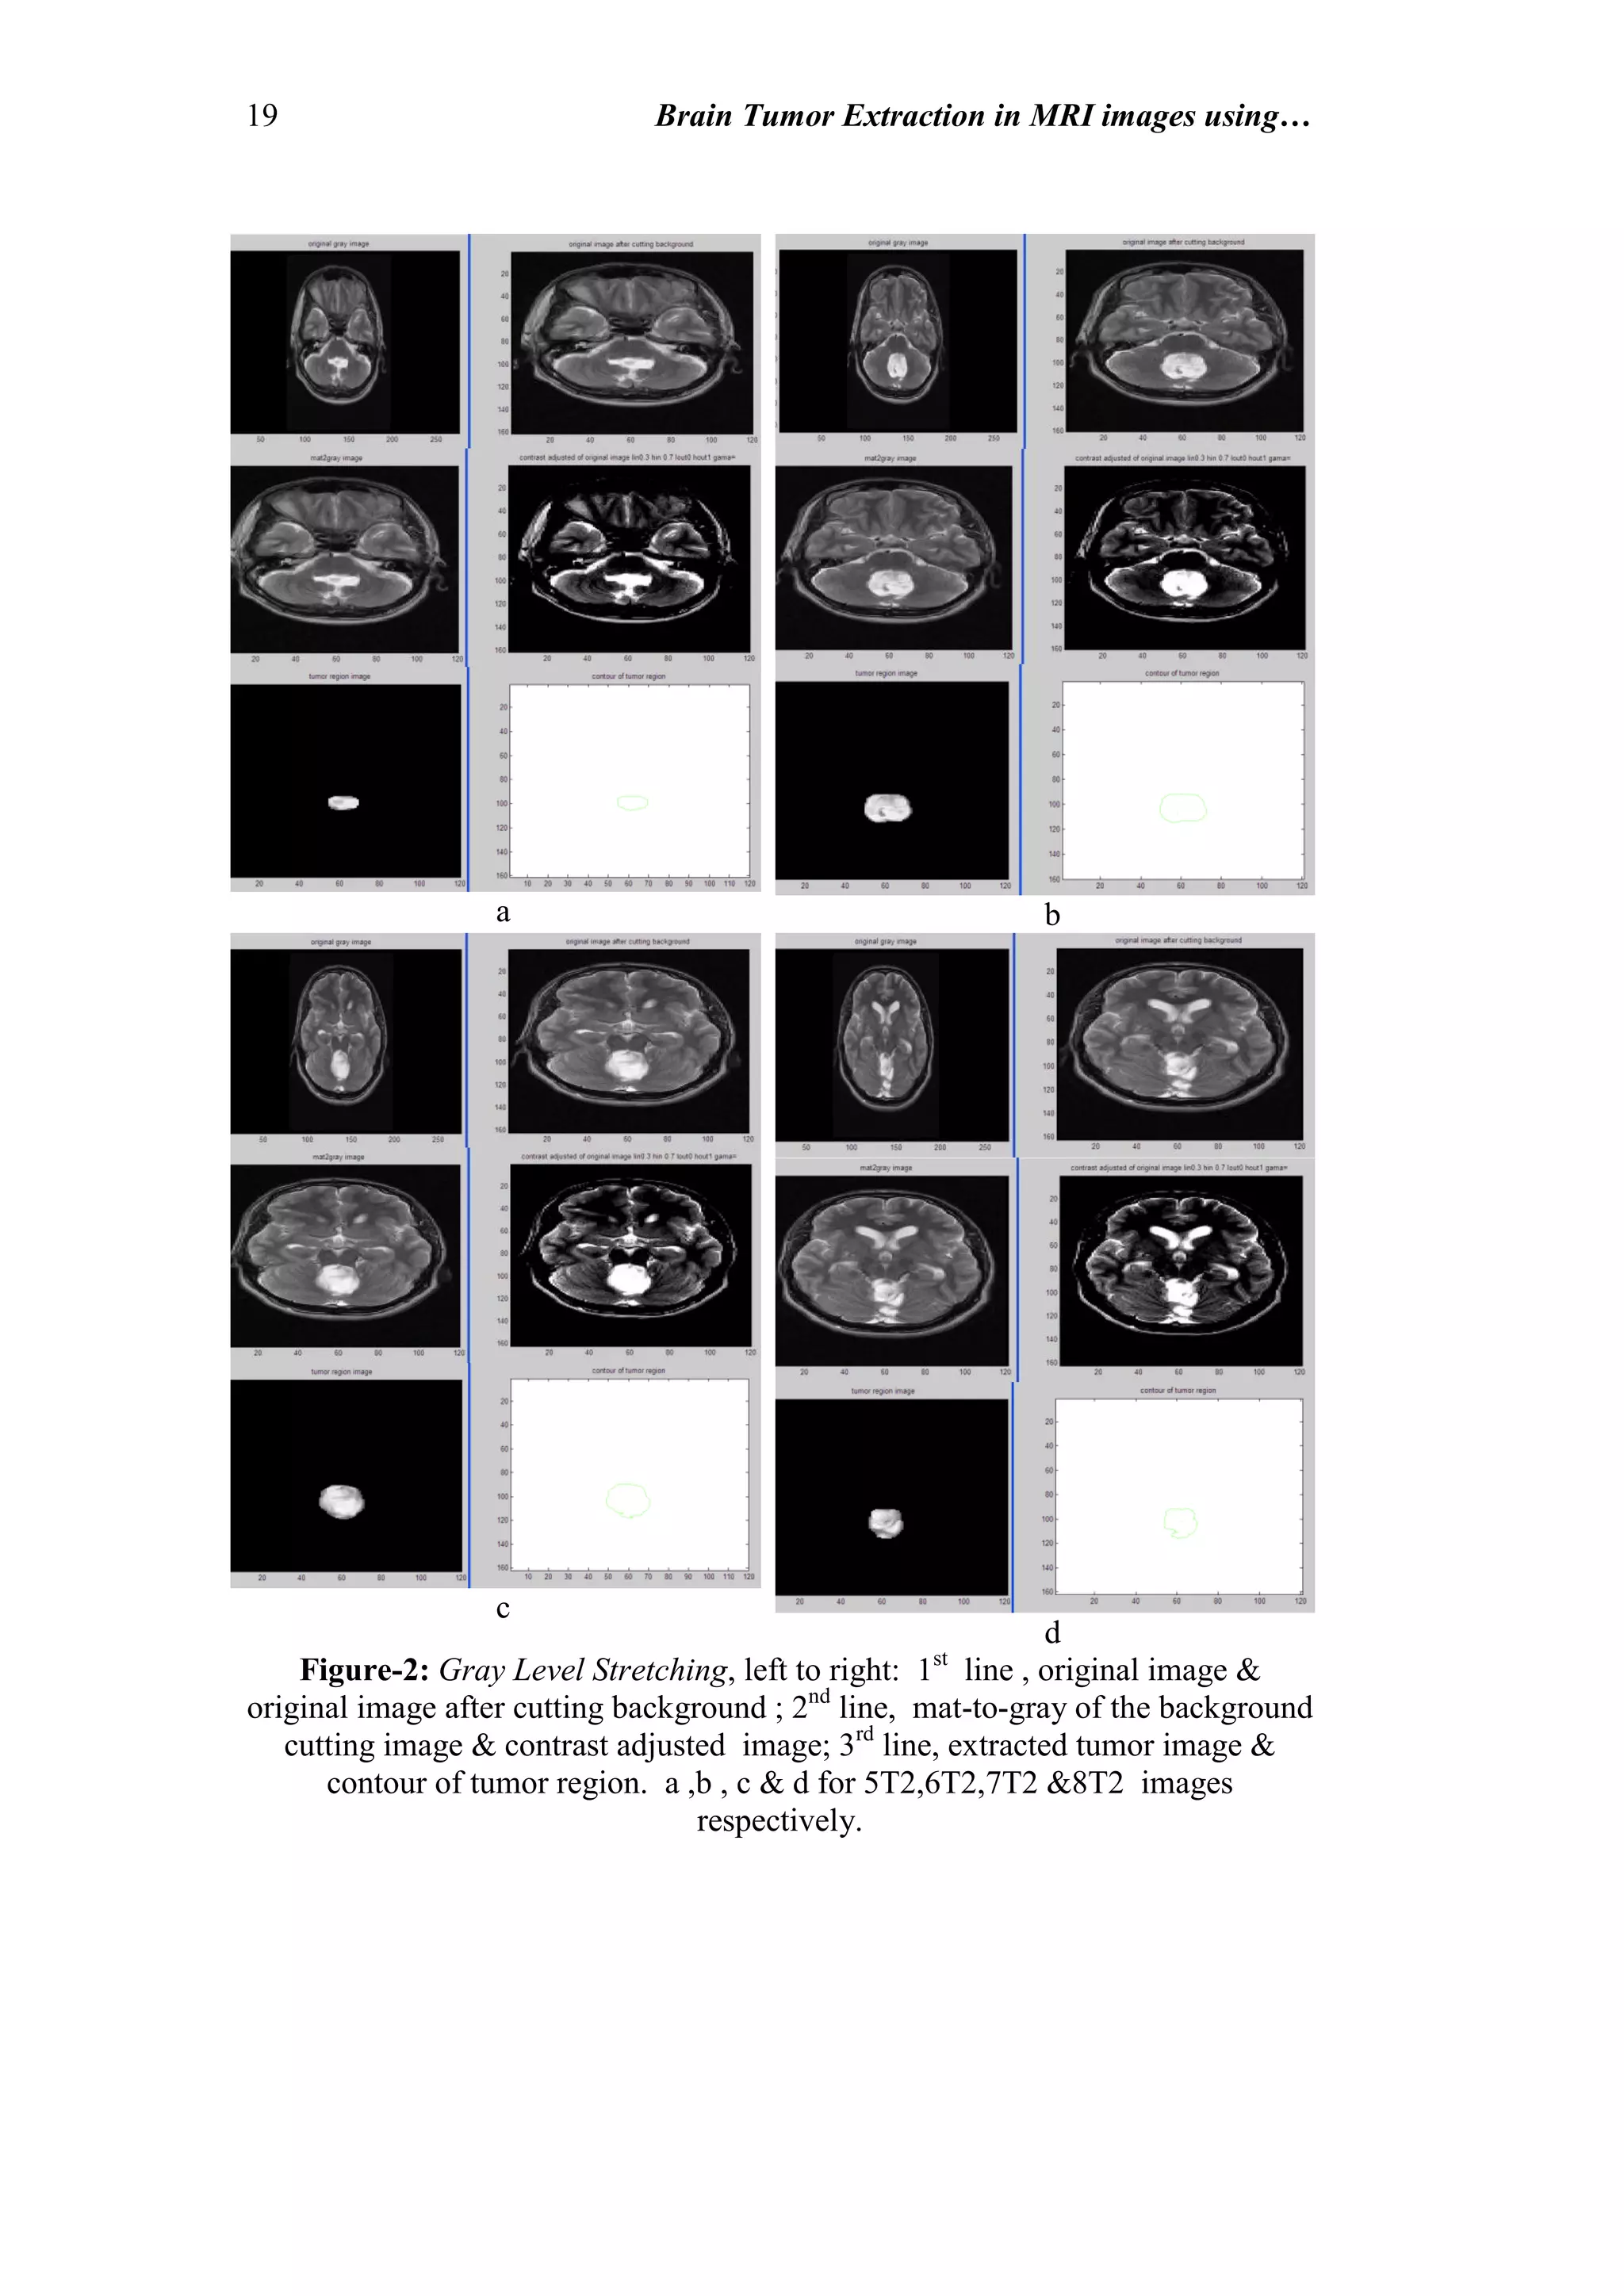

Figure-2: Gray Level Stretching, left to right: 1st

line , original image &

original image after cutting background ; 2nd

line, mat-to-gray of the background

cutting image & contrast adjusted image; 3rd

line, extracted tumor image &

contour of tumor region. a ,b , c & d for 5T2,6T2,7T2 &8T2 images

respectively.

10.1 Gray Level Stretching; includes

a. Gray Level Stretching: performing contrast adjustment to stretch the gray

level of the input image from the range [0.3-0.7] to the range [0 1].

b. Morphological Operation: after converting the image into binary form by

choosing threshold value (depending on the image intensity), many

morphological operations have been applied using structural element of 'disk-

shape', of 6-pixels diameter, these operations are:

1-Erosion: applied on the binary image.

2-Dilation: applied on the resultant image from the previous step.

The dilated image then convolutes with the input reduced intensity image (0.03

of its original intensity value).

c. Edge Detection

In this step, the Sobel operator is implemented on the resultant image from the

previous steps, followed by filling process to represent the final image of the

tumor. The last step involves contouring the tumor region, are illustrated in figs-

2&3.

d. Surface Area of the Tumor Region:

The last step was computing the surface area of the tumor region in pixel unit, as

listed Table-1. All the above processes have been applied without smoothing the

original image; the results are shown in fig-2.